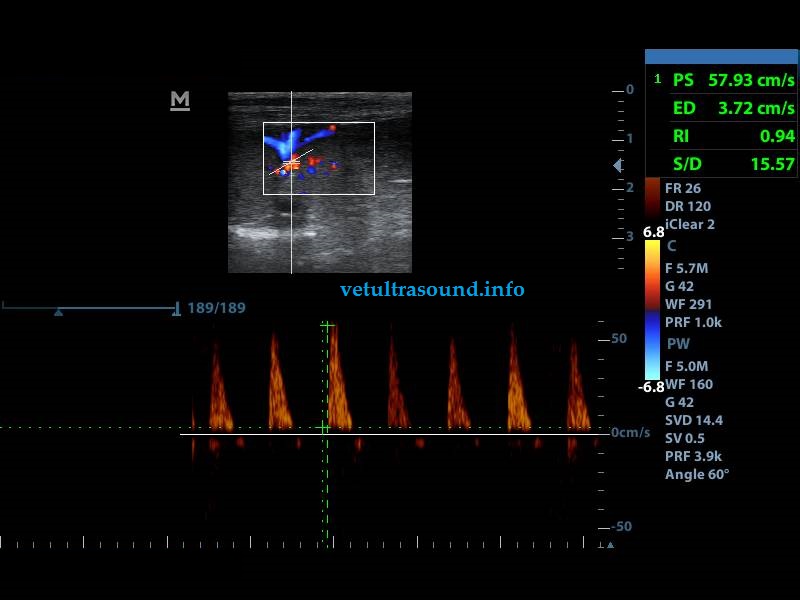

- Αύξηση του δείκτη αγγειακής αντίστασης (RI: 0.99 φυσιολογικά θα έπρεπε να είναι 0.6- 0.7).

- Μείωση της διαστολικής ροής των μεσολόβιων νεφρικών αρτηριών (Στοιχείο που δείχνει πως το παρέγχυμα του νεφρού είναι πιο σκληρό και περιορίζεται το εύρος διαστολής των αγγείων, πιθανά λόγω οιδήματος ή οξείας σωληναριακής νέκρωσης).

- Σε έρευνες στον άνθρωπο έχει βρεθεί πως όταν ο δείκτης αγγειακής αντίστασης στον νεφρό αυξάνεται πέρα του 0.8, η πρόγνωση για την διατήρηση της νεφρικής λειτουργίας είναι δυσμενής.

- Increased resistive index of the renal cortex arteries RI: 0.99

- Decrease of the diastolic flow in the renal arteries (Sign of increased stiffness of the renal parenchyma, probably due to edema or acute tubular necrosis).

- In human medicine a resistive index value of more than 0.8 is a negative prognostic factor.